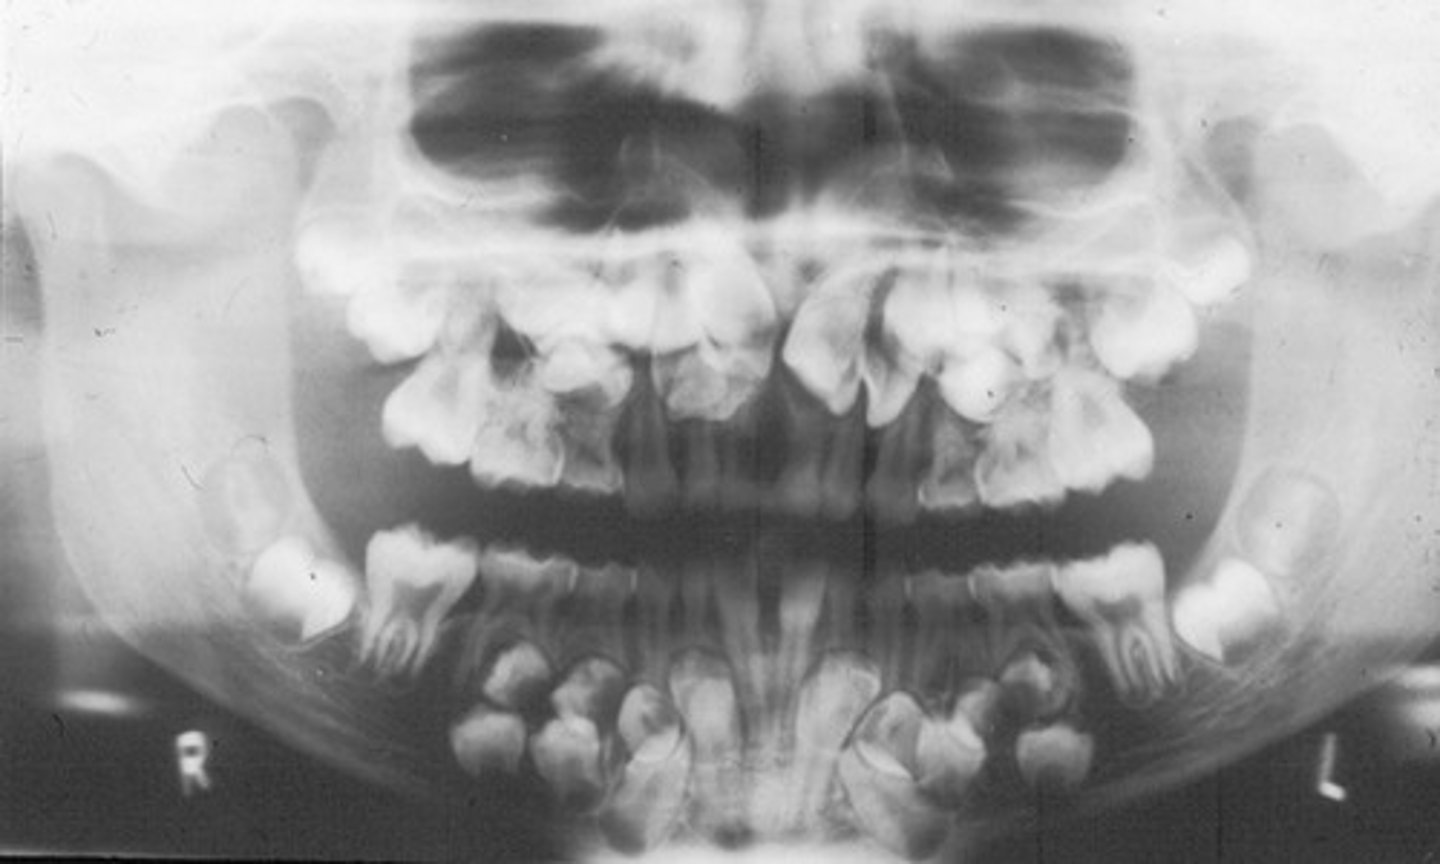

patient with reduced or missing teeth on a pan

ectodermal dysplasia

patient has supernumerary teeth (extra teeth) ... likely diagnosis?

cleiodcranial dysplasia